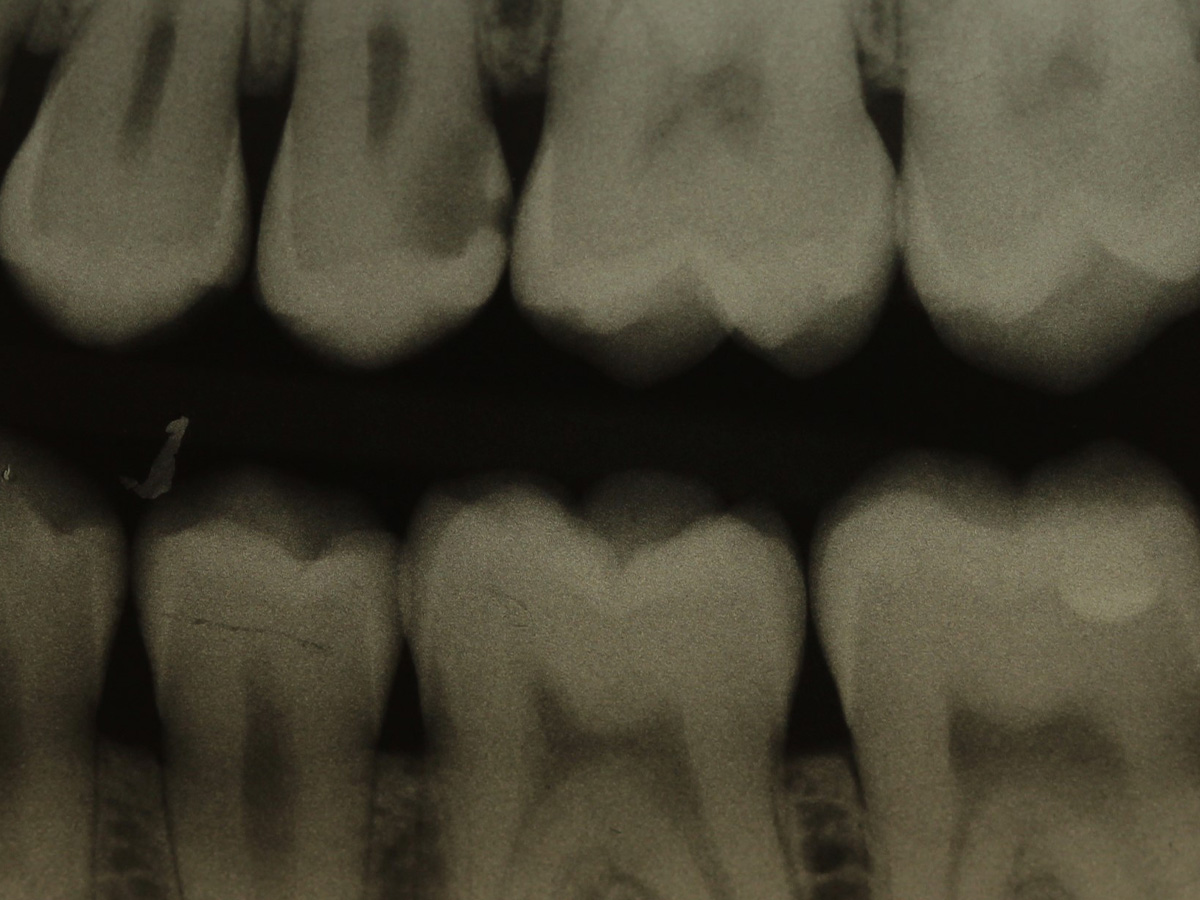

Abbildung 1

Bissflügelröntgenaufnahme, Approximalraumkaries an Zahn 25 distal